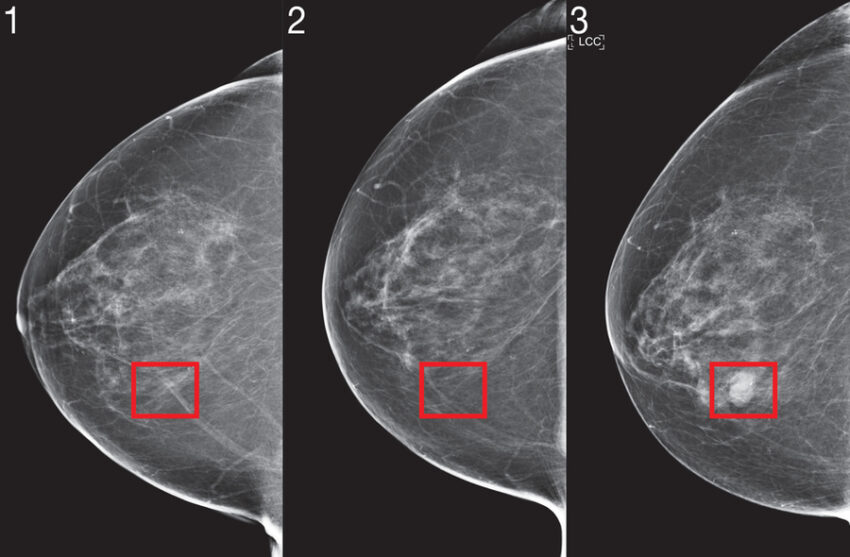

Araştırmacılar, risk modellemesinin kendine özgü gereksinimlerini yakalayacak şekilde yeni “Mirai” algoritmasını tasarladı. Mirai, hastanın riskini birden fazla gelecekteki zaman dilimi için aynı anda modelleyebiliyor ve mevcutsa yaş veya aile geçmişi gibi klinik risk faktörlerinden faydalanabiliyor. Algoritma ayrıca, mamografi makinesi tercihi gibi klinik ortamlardaki küçük farklılıklar karşısında bile tutarlı tahminler verecek şekilde geliştirildi.

Mirai, daha önceki çalışmada kullanılan Massachusetts General Hospital (MGH) veritabanındaki 200.000’den fazla tarama üzerinden eğitildi ve MGH, İsveç’teki Karolinska Enstitüsü ve Tayvan’daki Chang Gung Memorial Hospital’dan test verileriyle doğrulandı. Mirai şu anda MGH’da kullanılıyor ve araştırma ortakları modeli kliniklere entegre etmek için çalışıyor.

Mirai, önceki yöntemlere kıyasla tüm test verilerinde daha doğru sonuçlar verdi. MGH test setinde, model mevcut klinik standart olan Tyrer-Cuzick modeline göre yaklaşık iki kat daha fazla gelecekteki kanser vakasını tespit etti. Farklı ırk, yaş ve meme yoğunluğu gruplarında benzer performans gösterdi. Karolinska test setinde farklı kanser alt türleri için de tutarlılığını korudu.